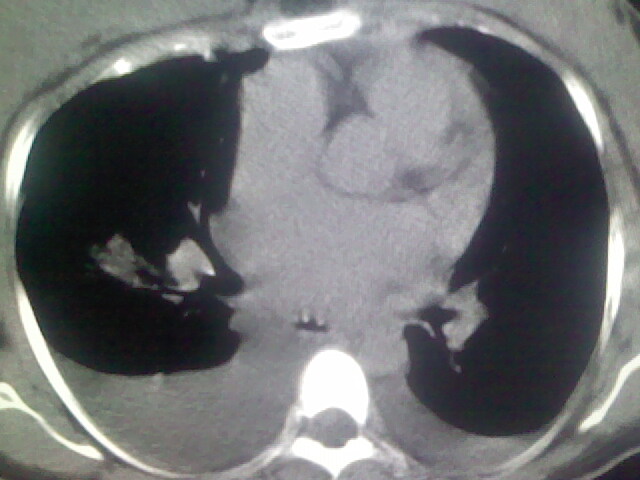

女,24,剖腹产后,突觉胸痛,干咳,不能平卧

肺水肿,双侧胸腔积液,双肺炎症。

肺水肿,双侧胸腔积液,心影增大.考虑妊娠心脏病

考虑产后心肌病,心功能不全,肺水肿,双侧胸腔积液。

考虑产后心肌病,心功能不全,肺水肿,双侧胸腔积液。不排除羊水栓塞可能。